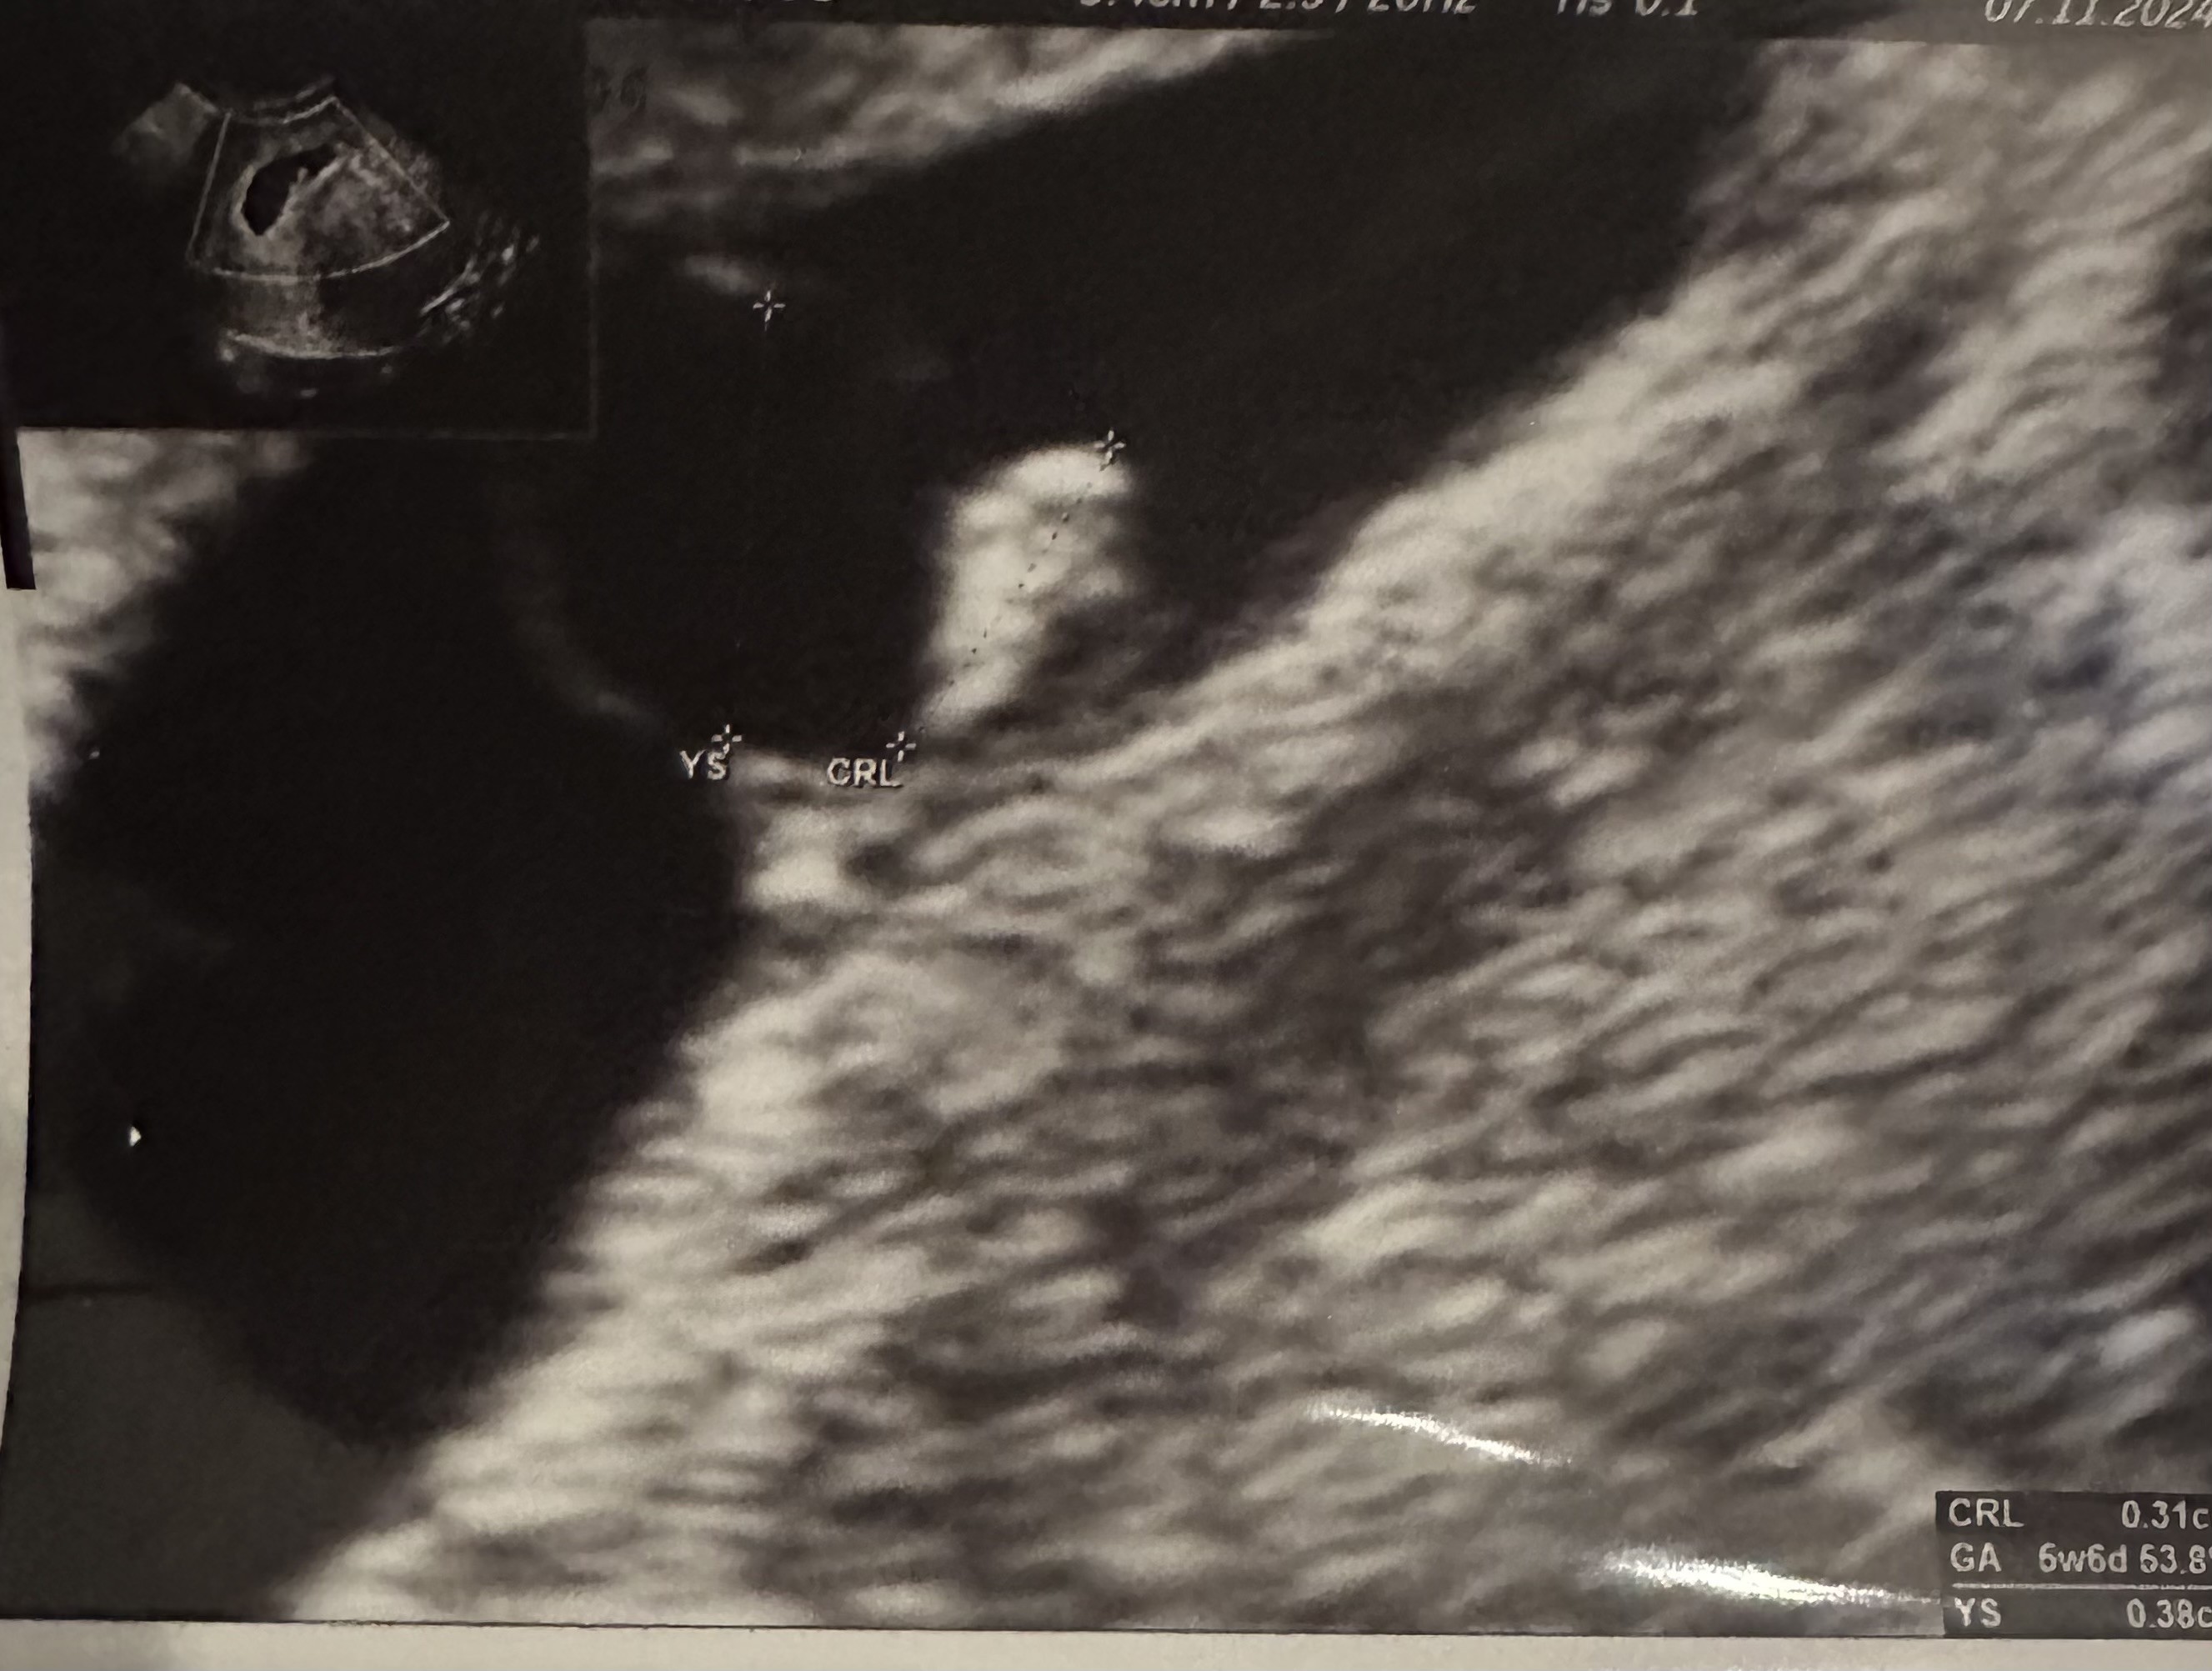

Właśnie wróciłam od gina.

Mam mieszane uczucia bo nie widziałam serca chociaż gin powiedziała „coś miga” ale że jeszcze wszystko małe ( a raczej słaby sprzęt w Medi) nie spr.

Dzidzia idealnie odpowiada 6+1 i mam być dobrej myśli, mam przyjść za tydzień - tyle, że nie ma wizyt… będę obserwować czy coś wpadnie, zadzwonię też na infolinię.

Wrzucam Wam zdjęcie USG w super medicoverowskiej jakości 🙈